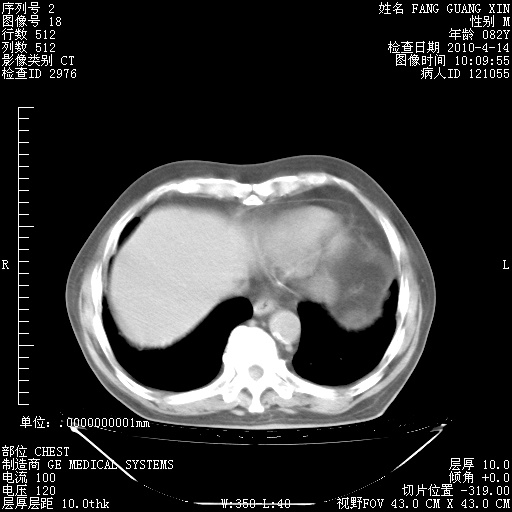

4月14日肺部CT